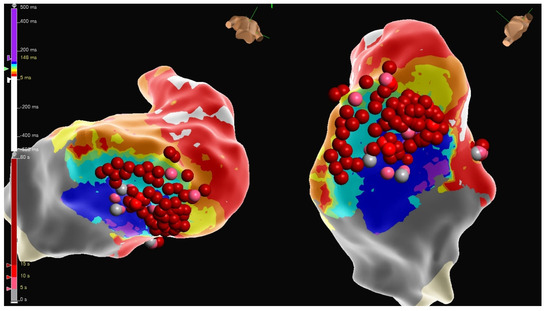

4.2.1. Cases

4.2.2. Case 1

4.2.3. Case 2